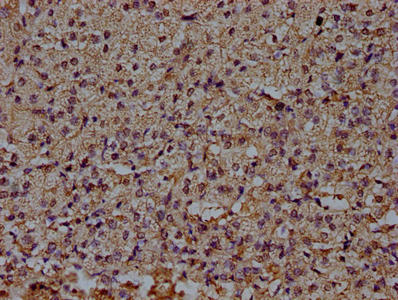

100 μg - PGP9.5 antibody [orb6713]Featured

ELISA, ICC, IF, IHC-P, WB

Human, Mouse, Rat

Rabbit

Polyclonal

Unconjugated